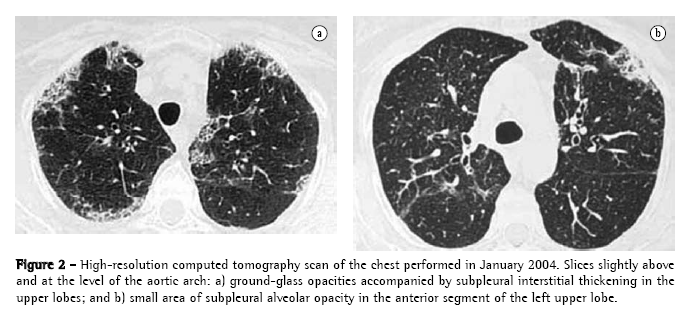

A chest X-ray performed four months after the initial medical visit showed areas of subpleural interstitial thickening in the upper lobes. An HRCT scan, performed concomitantly, revealed focal subpleural thickening of the intralobular and interlobular interstitium accompanied by faint ground-glass opacities, these alterations being present only in the upper lobes, and alveolar opacity being observed in the anterior segment of the left upper lobe (Figure 2). There were no mediastinal alterations. A control HRCT scan performed four months later showed no significant changes, except for an improvement in the area of alveolar opacity in the left upper lobe (Figure 3).

In the case in question, the findings were predominantly in the upper lobes and were principally subpleural. If only the HRCT findings are considered, the profile was highly suggestive of chronic eosinophilic pneumonia.(18-20) The favorable clinical evolution after the discontinuation of the medication, as well as the absence of recurrence after the discontinuation of the corticosteroid therapy, made it possible to establish a causal relationship between the pulmonary condition and the use of nitrofurantoin. The persistence of the imaging findings in the upper lobes translated to chronic interstitial alterations that were irreversible.